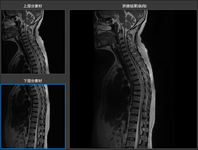

两个.dcm文件操作结果如下图所示。